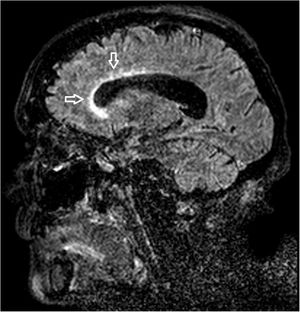

A 68-year-old woman with chronic bronchitis was admitted to the Intensive Care Unit at the start of the COVID-19 pandemic due to respiratory failure and bilateral lung infiltrates consistent with SARS-CoV-2 infection, though PCR testing proved negative on several occasions. During admission she suffered a progressive altered level of consciousness, requiring orotracheal intubation. Aspergillus lentulus was isolated from the bronchial aspirate. Lumbar puncture revealed: glucose 24 mg/dl, total proteins 133.6 mg/dl, leukocytes 136/µl and mononuclear cells > 95%. The brain CT scan showed no acute lesions and the brain MRI study revealed subependymal enhanced signal intensity around the frontal horn and atrioventricular zone of the lateral right ventricle (Figs. 1 and 2), with diffusion restriction in the apparent diffusion coefficient (ADC) study (Fig. 3). With the suspicion of fungal ventriculitis, PCR testing for Aspergillus spp. was performed in cerebrospinal fluid, with positive results.